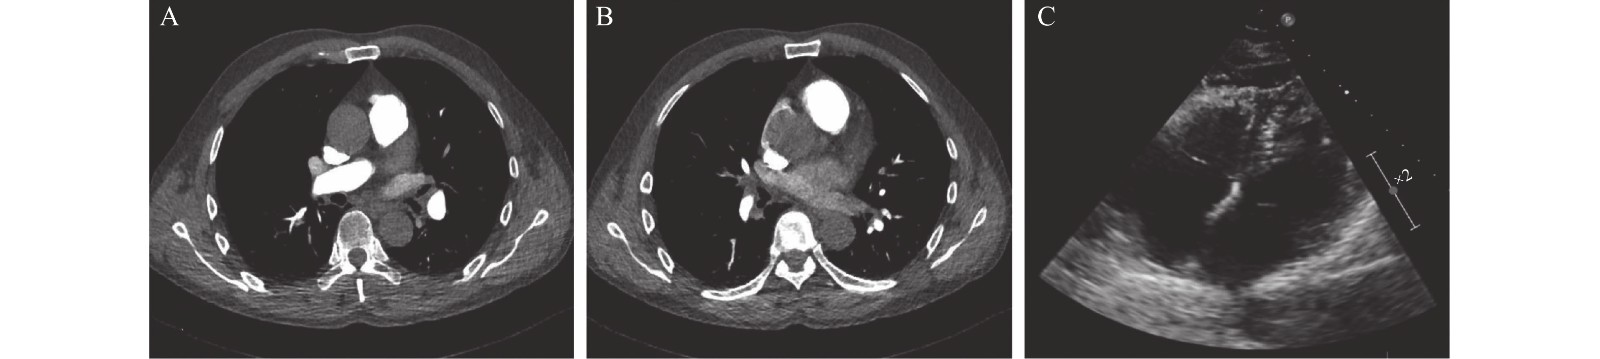

• Right heart thrombus (RHTh) with concurrent acute pulmonary embolism (PE) is rare and can seriously destabilize hemodynamics, leading to an emergency situation with high mortality. Diagnosis and treatment of RHTh with acute PE are not yet standardized. There are few reports of acute PE concurrent with RHTh and even less is known about patients with a right heart mural thrombus. For physicians, the diagnostic choice and treatment of these patients are particularly difficult due to the lack of knowledge. Here, we report a rare case of partial mural RHTh (type C RHTh) with acute PE. The mural mass in the right heart was initially diagnosed as atrial myxoma according to transthoracic echocardiography (TTE), and both pulmonary embolus and the mural mass were completely absorbed after administering Rivaroxiban. This case suggests that TTE alone is insufficient to identify and diagnoses a right heart mural mass such as this. However, novel oral anticoagulants may be effective at alleviating PE with type C RHTh.